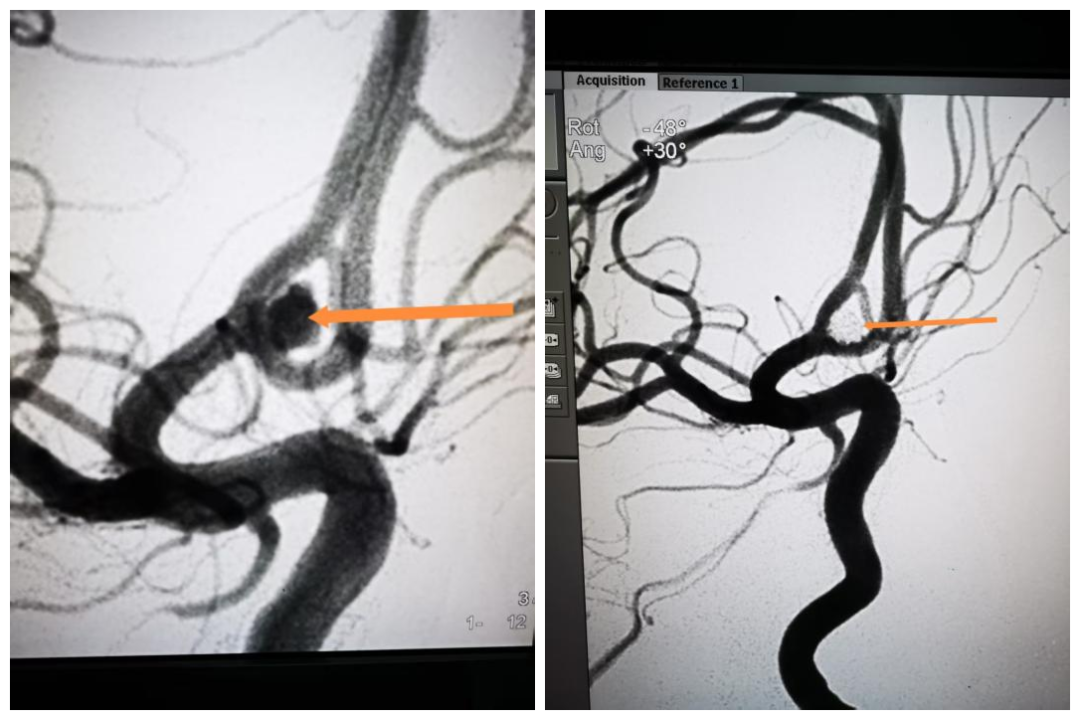

CT检查发现蛛网膜下腔出血,脑内血肿;进一步接受脑血管造影(CTA)检查,明确左侧大脑中动脉存在动脉瘤,瘤体破裂引发脑出血。 “从影像上看,动脉瘤已经破裂,整个脑子里弥漫着血。”陈飞宇记得,血管直径不过2mm,动脉瘤最长径却有4mm,在血流冲击下,破裂动脉瘤的破口就像肥皂泡一样脆弱易碎。出血导致颅内压持续升高,如果不尽快手术,可能会对脑组织、神经造成严重损伤。陈飞宇团队当机立断,精准判断病灶并行血管内介入治疗,经1个小时的手术,这枚埋藏在赵女士颅内的“定时炸弹”终于被成功扫除。

手术前后影像对比。

56岁的李先生最近也因为脑动脉瘤在宁波二院神经外科接受介入手术,不过他比赵女士要幸运得多,在瘤体破裂前就拆除了这颗“定时炸弹”。李先生是个“养生达人”,平时很注意身体,有定期体检的习惯,在近期一次检查中偶然发现一颗最长径达5mm的脑动脉瘤。陈飞宇评估后发现,动脉瘤不仅直径较大,而且形态不规则,破裂风险很大,建议接受预防性手术,堵塞瘤体。手术仅耗时半个小时,陈飞宇团队就为李先生堵住了血管瘤,术后3天患者就顺利康复出院。